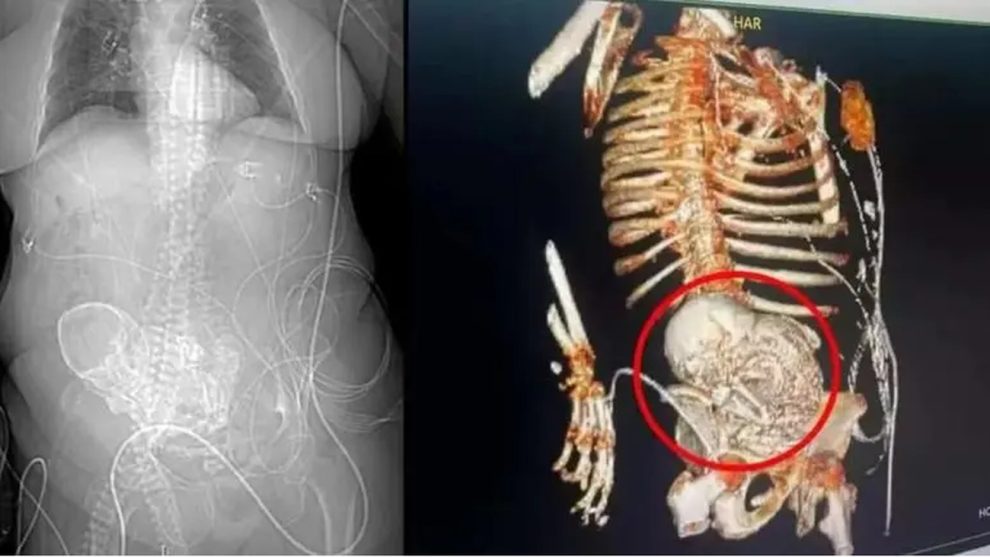

El cuerpo, en lugar de absorber o expulsar al feto, comienza a calcificarlo. Durante este proceso, el calcio comienza a deshidratar los tejidos, formando un fenómeno llamado cálculos. Esto puede ocurrir sin ningún síntoma evidente y sólo las pruebas de imagen pueden revelar su existencia.

Sin embargo, al no presentar síntomas, puede permanecer en el cuerpo por mucho tiempo, como le ocurrió a esta mujer de 81 años en Brasil. Aunque este fenómeno pueda parecer un mito, existen muchos casos registrados de esta extraña consecuencia. Diversas encuestas reflejan especialmente esta situación en las mujeres mayores.